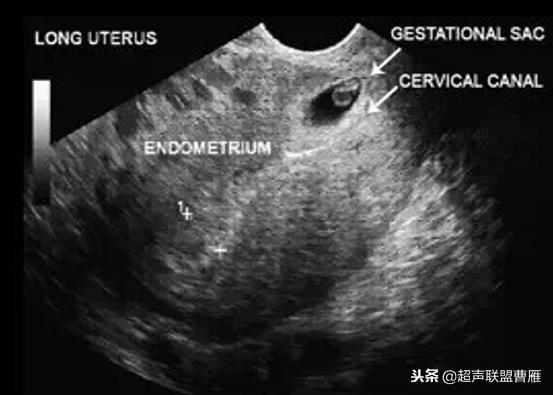

Ⅱ型孕囊胚胎停育型

1.子宫下段见变形妊娠囊,无胎心搏动,见扩张血管及多量血池

2.孕囊周围局部肌层血流信号丰富,可记录到类滋养层周围血流频谱

(Ⅱ型孕囊胚胎停育型)